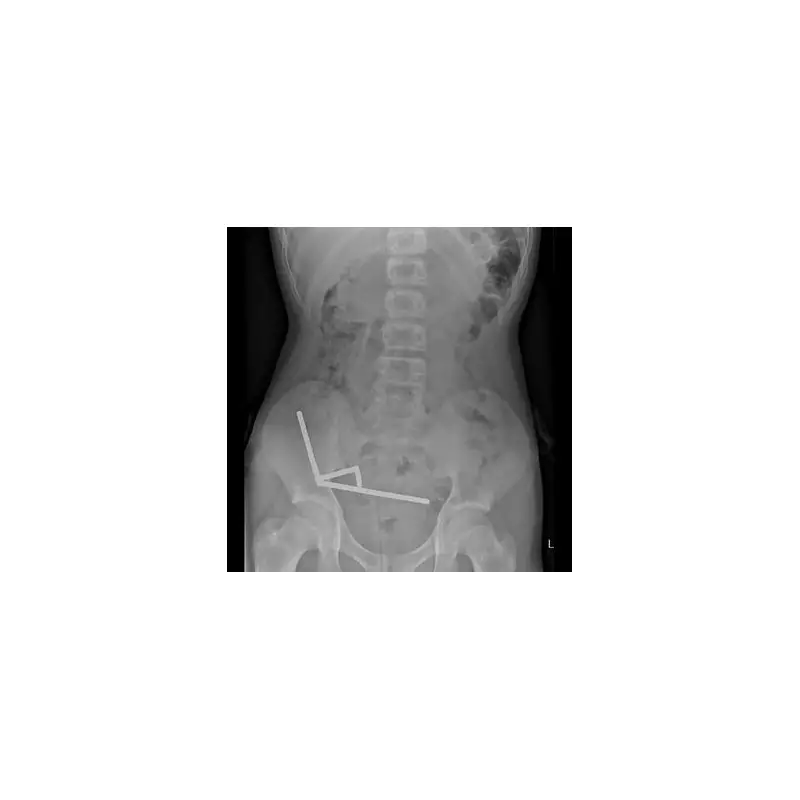

The impact caused severe damage to Harry's right wrist, completely shattering multiple bones. Paramedics rushed him to Manchester Royal Infirmary where surgeons delivered the grim news: he required immediate complex surgery to reconstruct his wrist.

"The doctors told me I'd broken my scaphoid and lunate bones in multiple places," Harry explained. "They had to insert metal plates and screws to put everything back together. The surgeon said it was one of the worst wrist fractures he'd seen from an e-scooter accident."